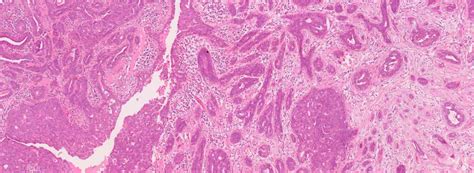

Hey guys, let’s dive into something super important today: breast cancer prediction . It’s a field where technology is making huge strides, and one of the most exciting areas is using deep learning , specifically with something called gated attention multimodal deep learning . Now, I know that sounds a bit technical, but stick with me, because understanding this can shed light on how we’re getting better at catching this disease early. When we talk about predicting breast cancer, we’re essentially trying to identify individuals who are at a higher risk of developing the disease, or even detecting it at its earliest, most treatable stages. This isn’t just about looking at one piece of information; it’s about piecing together a complex puzzle. That’s where multimodal learning comes into play. Instead of relying on a single type of data, like just mammograms, multimodal approaches integrate information from various sources. Think about it – we can analyze medical images (like mammograms and ultrasounds), patient history (age, family history, genetic markers), and even clinical notes. Each of these data types provides a unique perspective, and when combined, they can offer a much more comprehensive and accurate picture than any single source could provide alone. The challenge, though, is that not all this information is equally important all the time. Some bits of data might be crucial for one patient, while other bits are more relevant for another. This is where the gated attention mechanism becomes our secret weapon. It’s like a smart filter that learns to pay more attention to the most relevant pieces of information for each individual case, effectively weighing them differently. This allows the deep learning model to focus its ‘attention’ on the most critical features, leading to more precise predictions. So, when we combine the power of deep learning, the richness of multiple data sources (multimodal), and the intelligence of attention mechanisms, we get a formidable tool for breast cancer prediction. It’s a way to make sense of complex medical data and hopefully lead to earlier diagnoses, better treatment outcomes, and ultimately, save more lives. Pretty cool, right? Let’s break down how this fancy ‘gated attention multimodal deep learning’ actually works and why it’s such a game-changer in the fight against breast cancer.

Alright, so let’s get real about why multimodal data is such a big deal when we’re talking about breast cancer prediction . Imagine you’re a detective trying to solve a case. Would you just look at one tiny clue and make your decision? Nah, you’d gather as much evidence as possible: witness statements, forensic reports, security footage, the whole nine yards. That’s exactly what multimodal learning does for breast cancer. Instead of just feeding a computer a stack of mammograms, we’re giving it a whole dossier of information. This can include radiological images like mammograms, MRIs, and ultrasounds, which are the traditional bread and butter of breast cancer screening. But it doesn’t stop there! We also throw in clinical data , which is all the juicy stuff from a patient’s medical record: their age, how many times they’ve given birth, whether they’ve had hormone therapy, their family history of cancer, and crucially, any known genetic mutations like BRCA1 or BRCA2. On top of that, we can even process textual data from doctors’ reports and pathology notes. Each of these data types brings something unique to the table. Images show us the physical manifestations of potential tumors or abnormalities. Clinical and genetic data give us insights into individual risk factors and predispositions. Textual data can capture nuanced observations that might not be immediately obvious in structured data fields. The magic happens when a deep learning model learns to correlate and integrate these different streams of information. It can identify patterns that a human might miss, or that are only apparent when multiple data points are considered together. For instance, a subtle abnormality on a mammogram might be flagged as higher risk if the patient also has a strong family history or a specific genetic marker. Conversely, a slightly denser area on an image might be considered less concerning if other factors indicate a low risk. This holistic approach is far more robust than relying on a single data modality. It reduces the chances of false positives (telling someone they might have cancer when they don’t) and false negatives (missing a cancer that is actually there), both of which have significant consequences for patients. By leveraging the power of diverse data sources, we can build prediction models that are more accurate, more personalized, and ultimately, more effective in the early detection and management of breast cancer. It’s like giving the AI a superpower to see the whole picture, not just a small slice of it, making it a true asset in our fight against this disease.